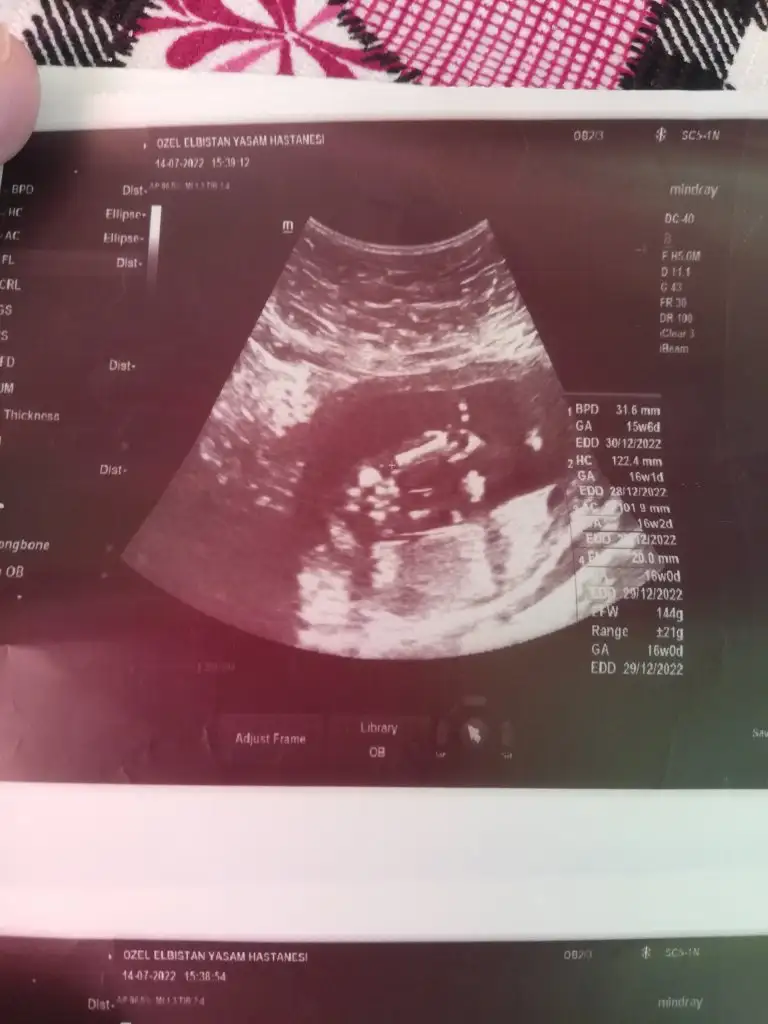

dr soylemeden siz gorun genital nub teorisi ( bebegin cinsiyeti)

Merhaba hanımlar tahmin alabilir miyim 12+2

Doktor birtürlü emin olamıyor ya nasıl iş anlamadım erkek testisi göremiom dedi kıza benzio ama emin değilim dio kızdır herlde ya

17 haftalık olmuş daha nasıl göremedi anlamadım ilginçmiş valla. Başka bir doktora da gitseydiniz keşke bende perşembe günü gideceğim bakalım bir şey öğrenebilecek miyim